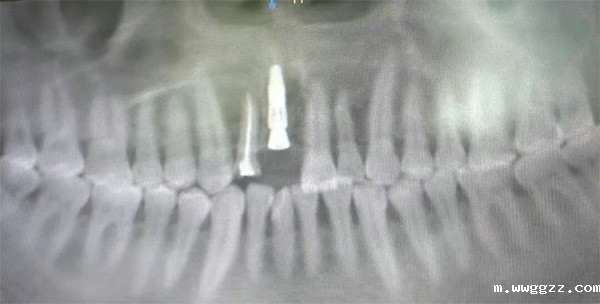

1、12成功实施根盾技术。该技术通过保留患者牙根的部分片断,如同树立一道“屏障”,最大限度地维护了缺牙区天然的软硬组织形态,为后期冠修复获得媲美天然牙的牙龈轮廓奠定了坚实基础,被誉为前牙美学种植的“高阶技术”。

2、21行即刻种植术+GBR骨增量技术。在拔牙后立即于新鲜拔牙窝内植入种植体,显著缩短了治疗周期,并有效避免牙槽骨的生理性吸收萎缩。此次带教展示的“根盾术+即刻种植+GBR”练习治疗策略,是对“以修复为导向,以美学为核心”现代种植理念的完美诠释,让我院医生近距离学习如何在前牙这一“门面”区域,实现功能与美学的统一。